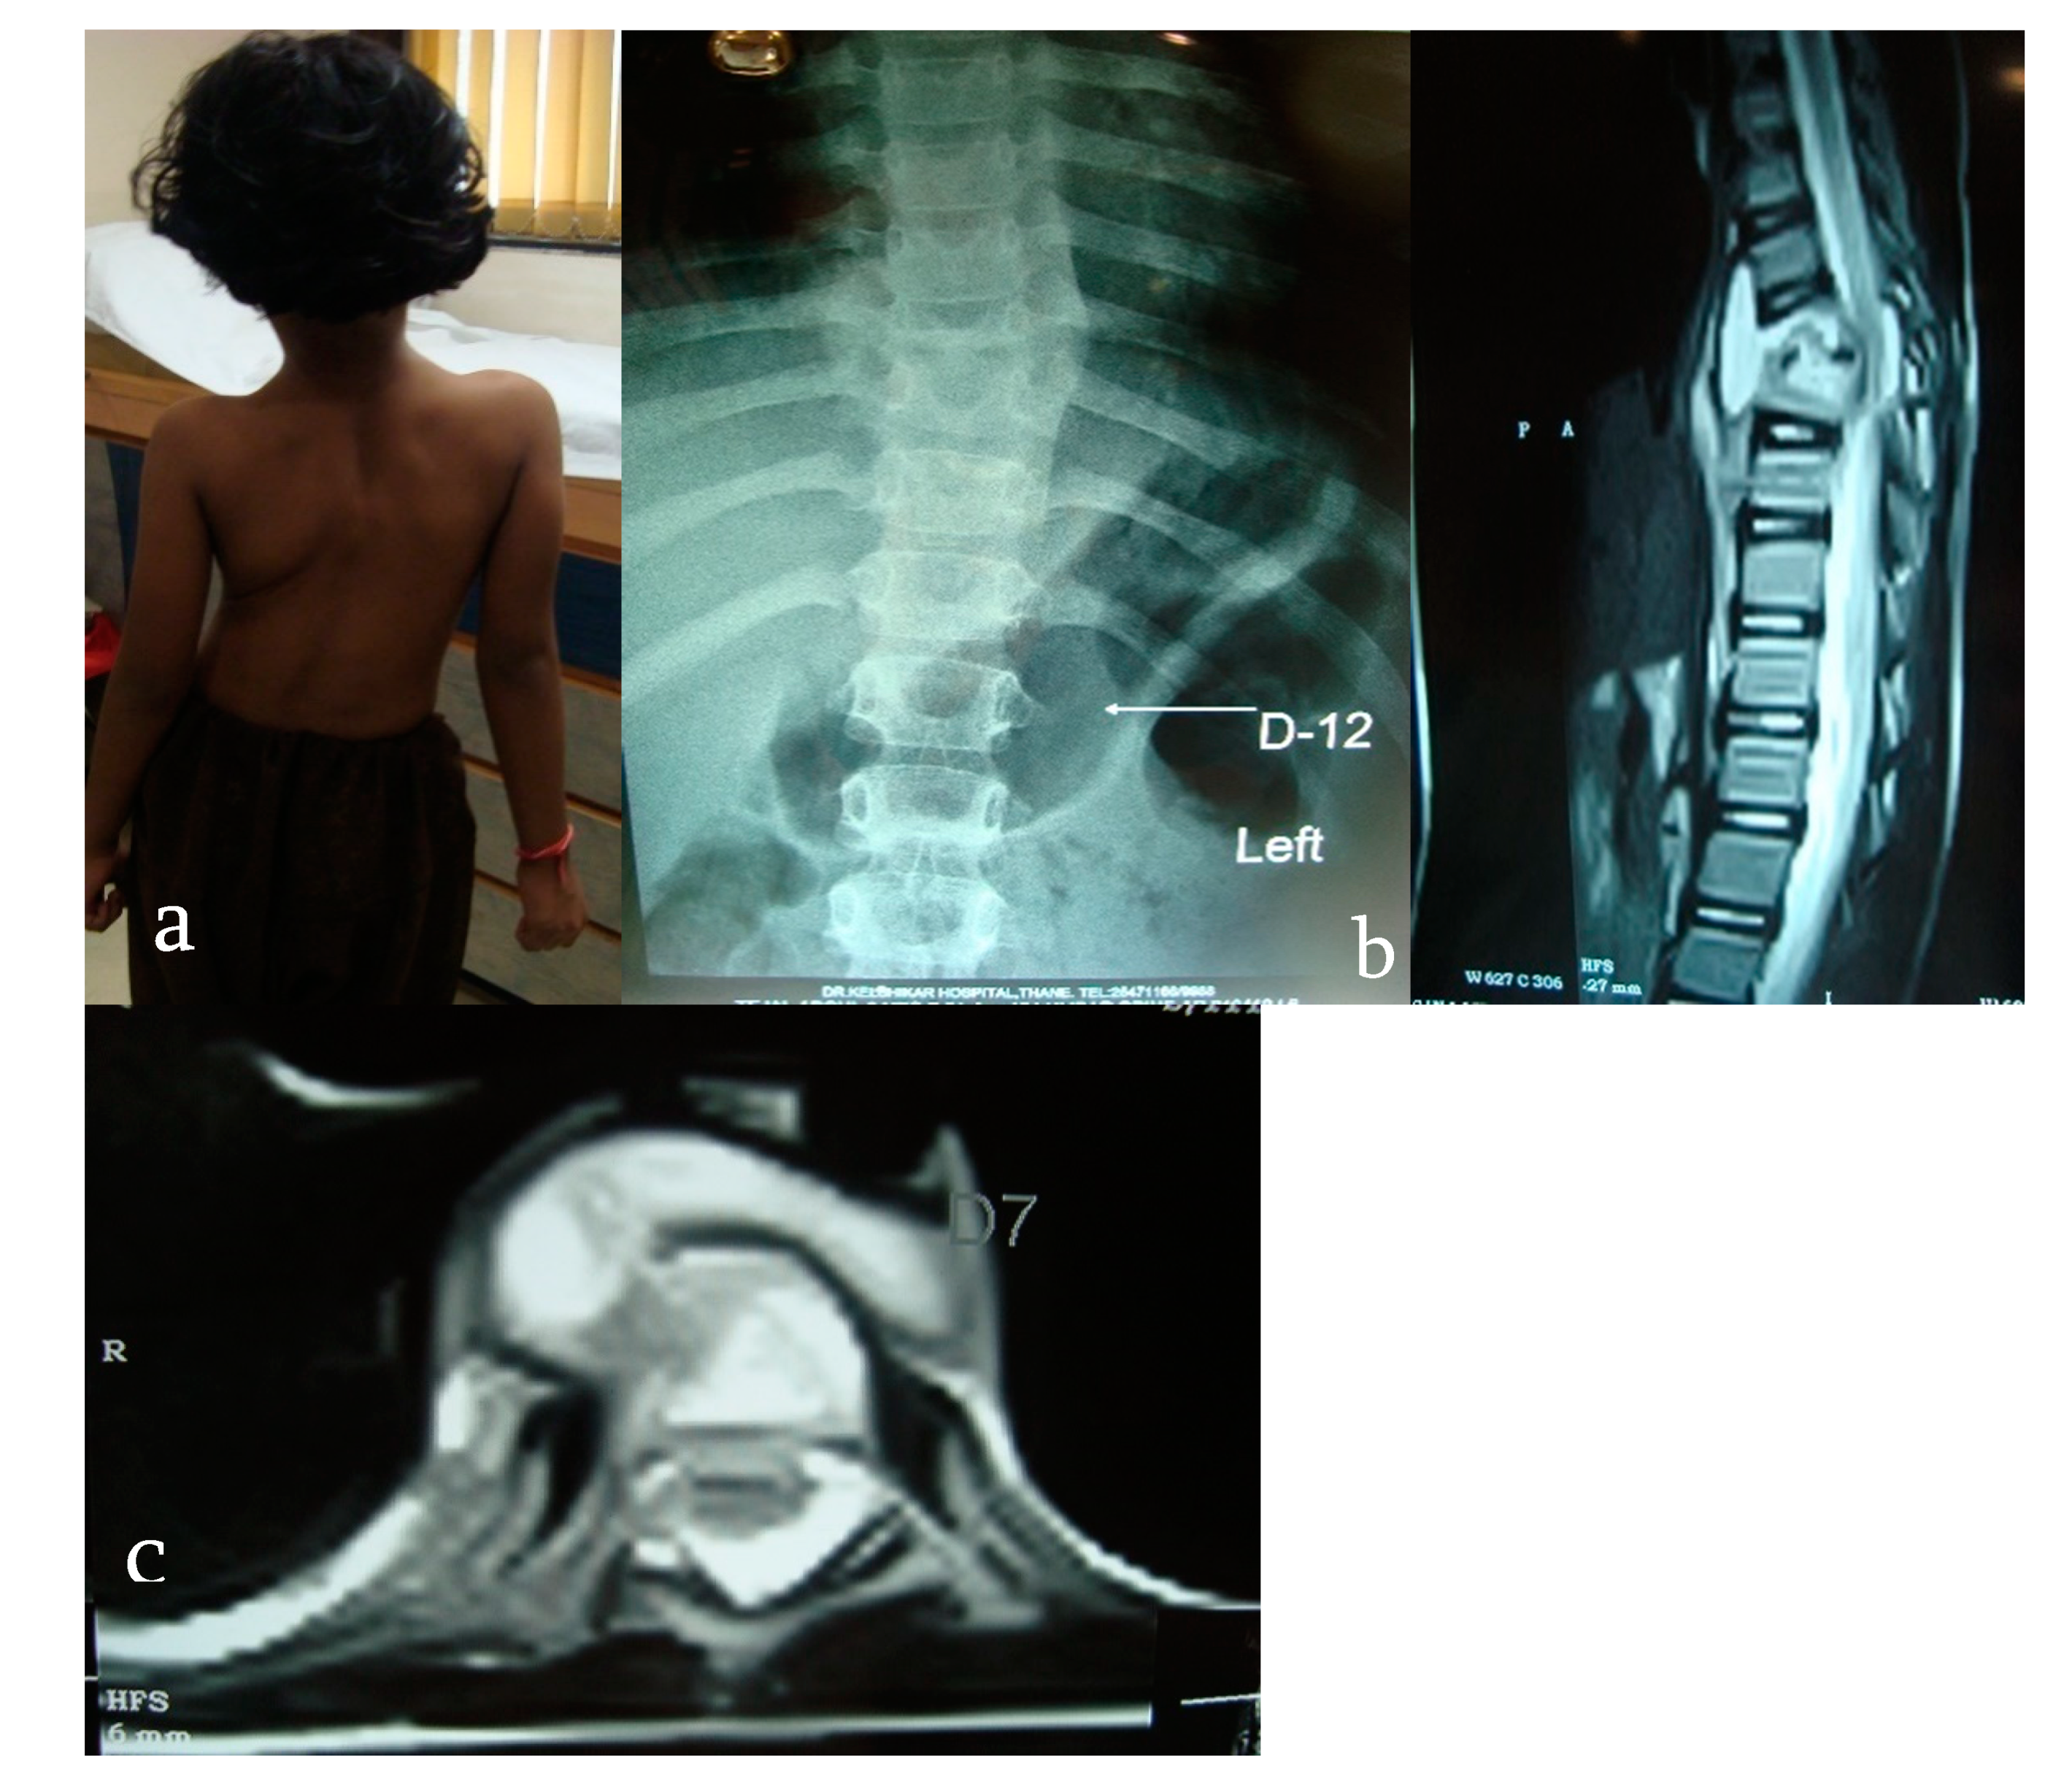

- Wagh, Y.; Reddy, R.; Gundavda, M.; Agarwal, M.; Agashe, V.M.; Bajwa, S. Tuberculosis (T.B.) masquerading as tumor. An 8-year study on 25 cases of long bone tuberculosis presenting as tumors. SICOT-J 2020, 6, 14. [Google Scholar] [CrossRef] [PubMed]